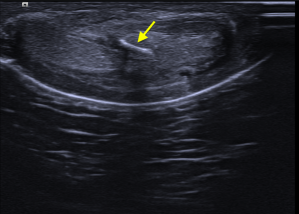

334. La Rete Testis.

Cuando vemos una colección de pequeñas imágenes anecoicas en él mediastino testicular.

Ecogénicamente tiene aspecto psudotubular, anecoico con zonas que simulan quistes intraparenquimatosos y que de debe al taponamiento parcial o total de los ductos eferentes.

Se diferencia de la Enfermedad displásica quística de la rete Testis porque esta es una figura patológica infantil y se asocia a malformaciones de tipo urológico.

Corte longitudinal del teste

Corte transversal del teste

Doppler

De aparición tardía en mayores de 50 años, bilateral de forma habitual, hasta en un 70% aproximadamente y típicamente asimétrico.

Es una entidad benigna y su importancia radica en que sea diferenciada de otro tipo de patologías malignas, como la neoplasia testicular de predominio quístico.

La ecografía es el prueba Gold Standard para su diagnóstico.